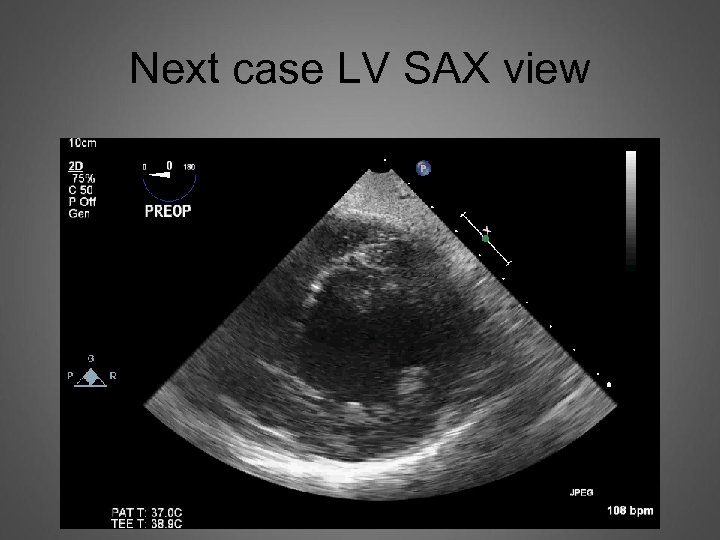

Next case LV SAX view

Now LV looks like this